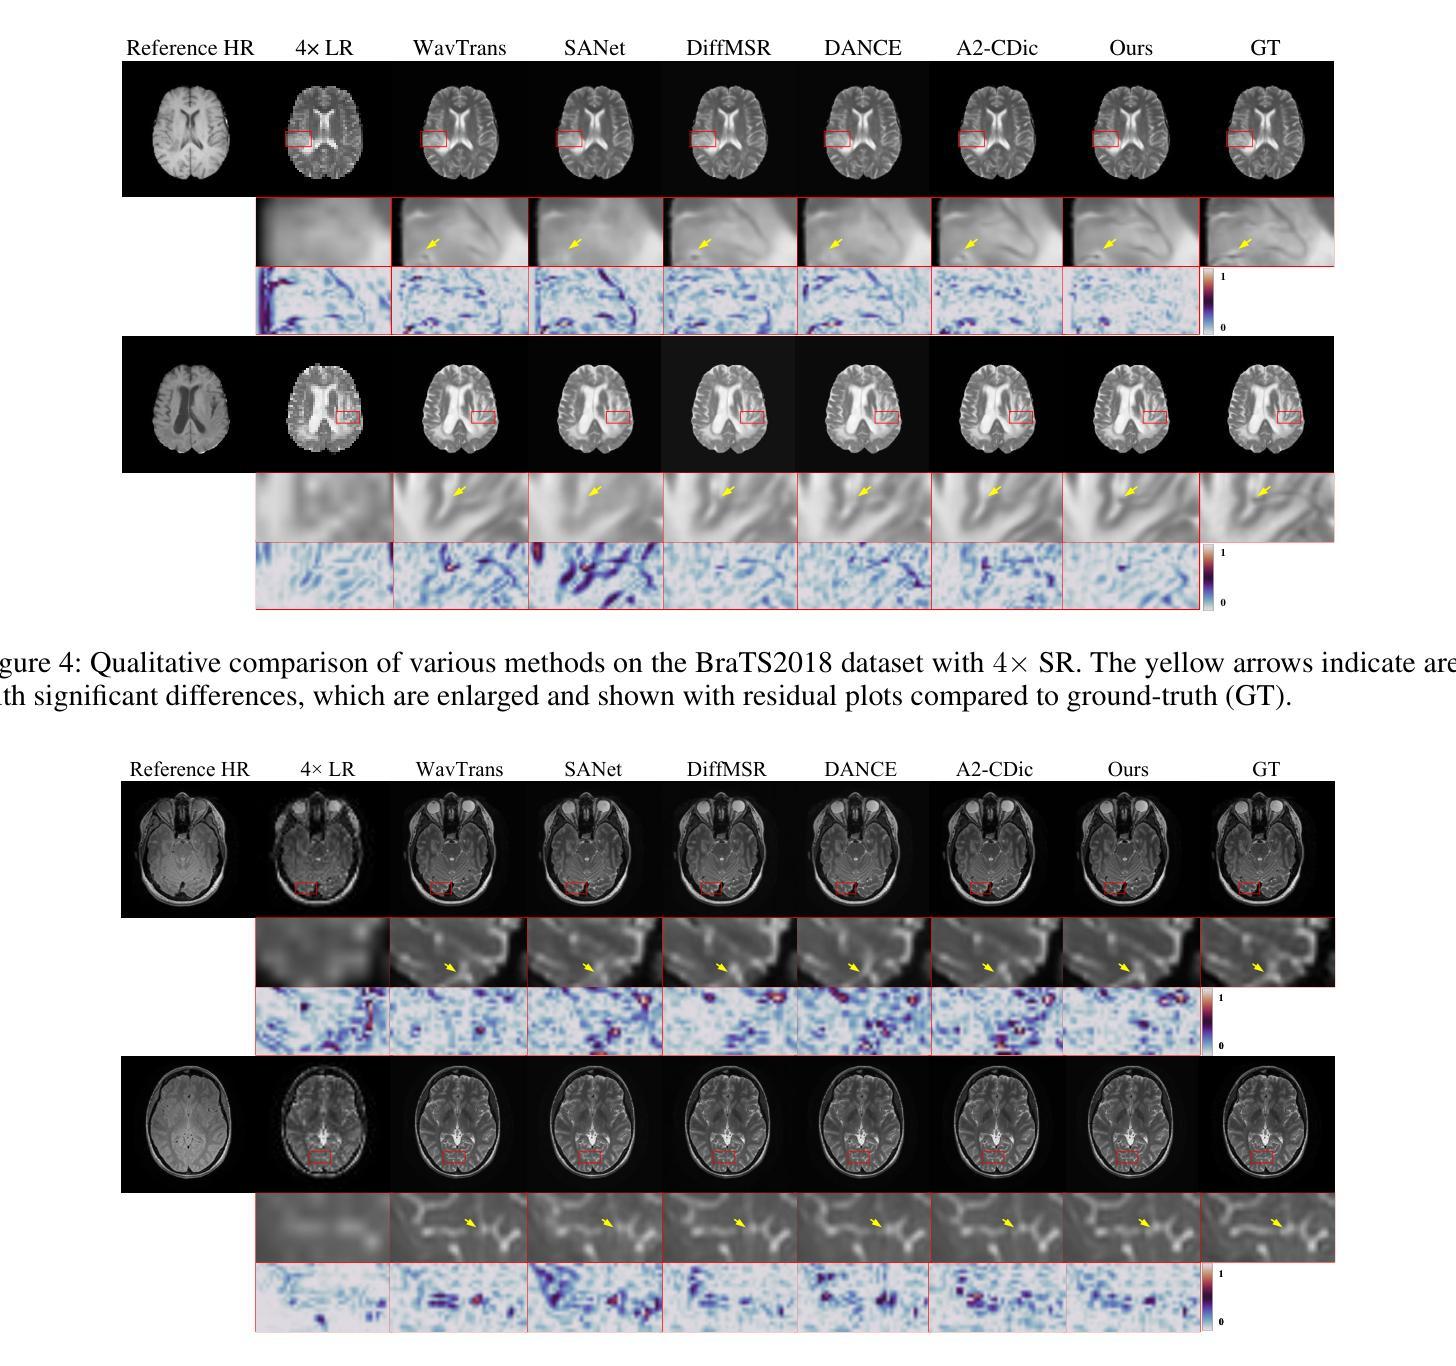

Multi-contrast magnetic resonance imaging (MRI) super-resolution intends to reconstruct high-resolution (HR) images from low-resolution (LR) scans by leveraging structural information present in HR reference images acquired with different contrasts. This technique enhances anatomical detail and soft tissue differentiation, which is vital for early diagnosis and clinical decision-making. However, inherent contrasts disparities between modalities pose fundamental challenges in effectively utilizing reference image textures to guide target image reconstruction, often resulting in suboptimal feature integration. To address this issue, we propose a dual-prompt expert network based on a convolutional dictionary feature decoupling (CD-DPE) strategy for multi-contrast MRI super-resolution. Specifically, we introduce an iterative convolutional dictionary feature decoupling module (CD-FDM) to separate features into cross-contrast and intra-contrast components, thereby reducing redundancy and interference. To fully integrate these features, a novel dual-prompt feature fusion expert module (DP-FFEM) is proposed. This module uses a frequency prompt to guide the selection of relevant reference features for incorporation into the target image, while an adaptive routing prompt determines the optimal method for fusing reference and target features to enhance reconstruction quality. Extensive experiments on public multi-contrast MRI datasets demonstrate that CD-DPE outperforms state-of-the-art methods in reconstructing fine details. Additionally, experiments on unseen datasets demonstrated that CD-DPE exhibits strong generalization capabilities.

多对比度磁共振成像(MRI)超分辨率技术旨在利用从不同对比度获取的高分辨率(HR)参考图像中的结构信息,从低分辨率(LR)扫描中重建高分辨率图像。此技术可增强解剖细节和软组织分化,对于早期诊断和临床决策至关重要。然而,不同模式之间固有的对比度差异,在有效利用参考图像纹理以指导目标图像重建方面构成了根本挑战,通常导致特征融合不佳。为了解决这个问题,我们提出了一种基于卷积字典特征解耦(CD-DPE)策略的多对比度MRI超分辨率双提示专家网络。具体来说,我们引入了一个迭代卷积字典特征解耦模块(CD-FDM),将特征分离为跨对比度和内对比度成分,从而减少冗余和干扰。为了充分融合这些特征,我们提出了一种新型的双提示特征融合专家模块(DP-FFEM)。该模块使用频率提示来指导选择相关的参考特征,并将其合并到目标图像中,而自适应路由提示则确定融合参考和目标特征的最佳方法,以提高重建质量。在公共多对比度MRI数据集上的广泛实验表明,CD-DPE在重建细节方面优于现有先进技术。此外,在未见数据集上的实验表明,CD-DPE具有较强的泛化能力。